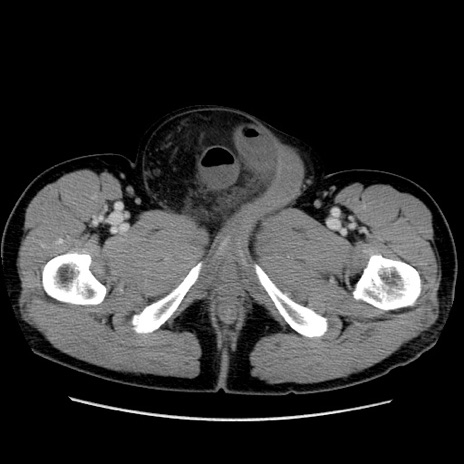

症例34(横断像)

【主訴】右鼠径部膨隆

【現病歴】1年程前より右鼠径部膨隆あり。自己にて還納可能だったため放置していた。3時間前より右鼠径部の脱出を認め、還納困難となり受診。

【既往歴】高血圧

【身体所見】右鼠径部に小児頭大の膨隆あり。弾性硬であり、用手還納は困難。左鼠径部にも膨隆を認める。脱出はなし。

【データ】WBC 15500、CRP 測定なし